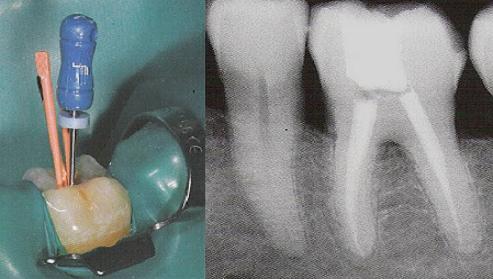

* Indepartarea tesutului vasculo-nervos (viu sau necrotic) din interiorul dintelui sau indepartarea unei obturatii de canal incorecte; * Dezinfectarea canalului radicular; * Largirea mecanica a canalului radicular; * Obturatia canalului radicular (umplerea si sigilarea canalului radicular cu gutaperca si pasta pentru sigilat); * Reconstituirea corono radiculara (metalica sau cu pivot din fibra de sticla).